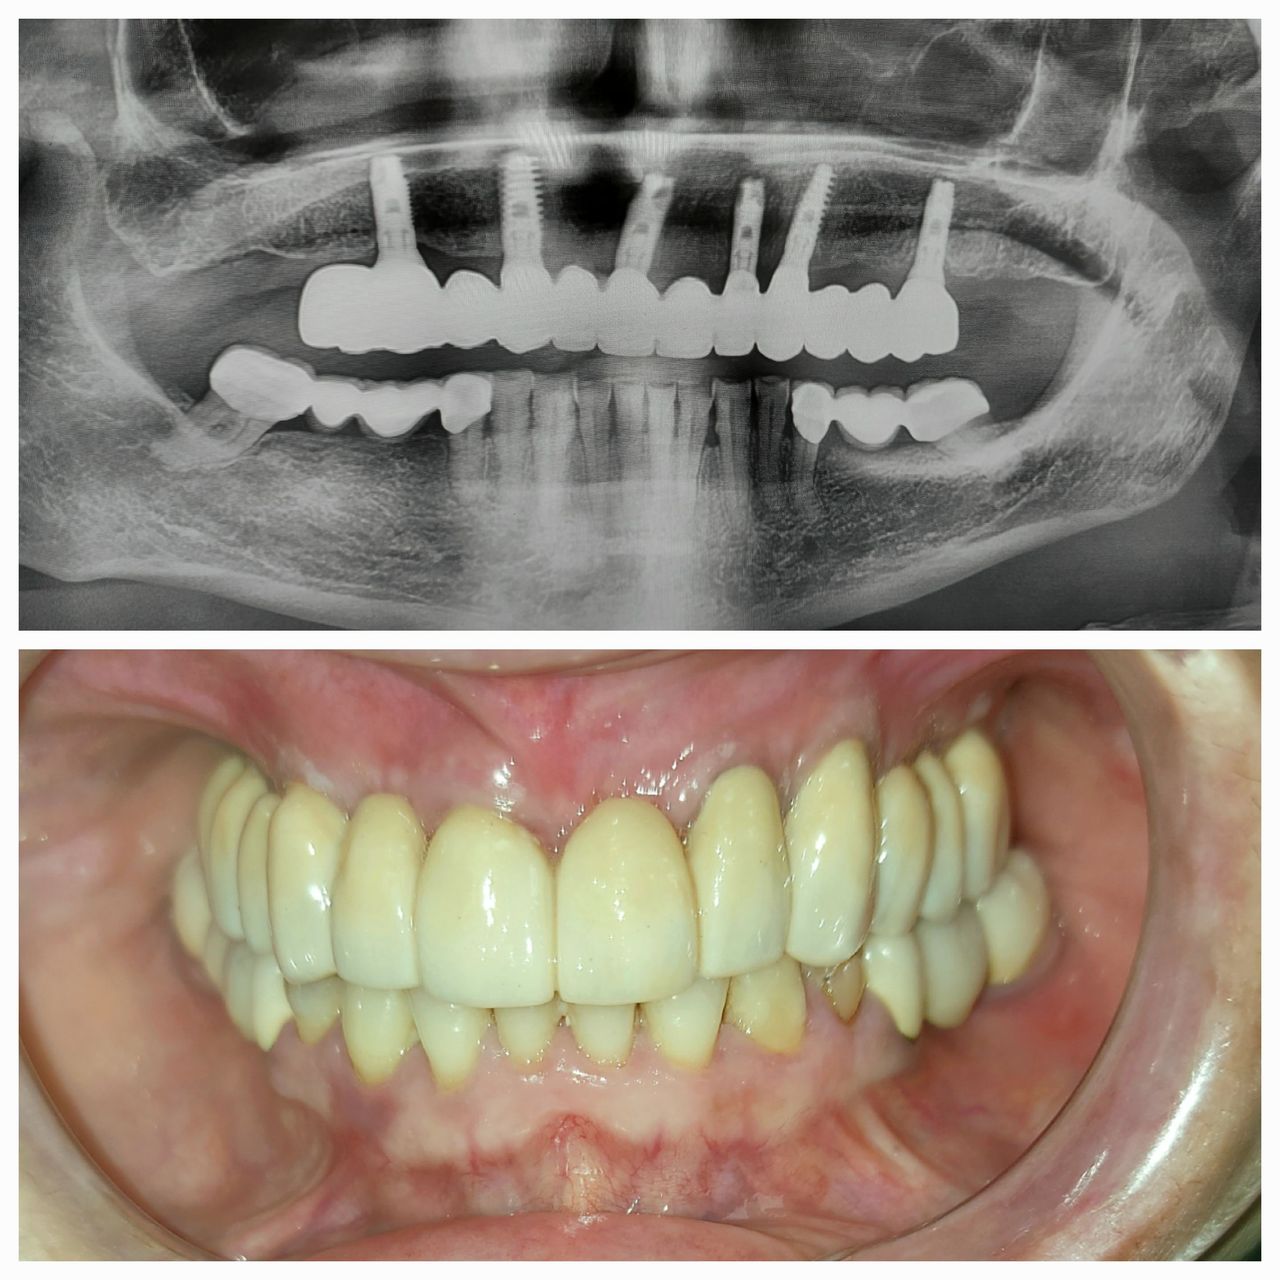

Il Dottor Lorenzo Paolo Bottini si laurea con il massimo dei voti e la lode in odontoiatria e protesi dentaria presso l'università degli studi di Roma Tor Vergata nel 2006. Si interessai da subito alla chirurgia orale e all'implantologia, frequentando come volontario i reparti di chirurgia orale e pronto soccorso del Policlinico di Tor Vergata e dell'ospedale Sandro Pertini fino al 2009. Successivamente consegue con il massimo dei voti la specializzazione universitaria in chirurgia odontostomatologica ed implantologia presso l'università degli studi di Chieti G. D'Annunzio. Negli stessi anni collabora come assistente ricercatore con il dipartimento di scienze orali diretto dal Prof. Adriano Piattelli, collaborando alla realizzazione di studi clinici e di pubblicazioni in materia di implantologia a carico immediato. Nel 2015 rileva lo studio dentistico di famiglia, aperto ad Albano Laziale dalla madre, Dott.ssa Maria Gabriella Di Felice, ed apre il centro odontoiatrico ProSmile, attrezzato con le più moderne tecnologie odontoiatriche (Radiografie digitali, Radiografie 3D, Scanner intraorali, laser odontoiatrici, apparecchiatura magnetica e piezoelettrica per la chirurgia orale) in cui opera insieme ad un team di collaboratori esperti, selezionati nel corso degli anni, per fornire ai pazienti soluzioni efficaci in tutte le branche odontoiatriche. Il Dottor Bottini svolge attività di relatore e di specialista clinico per diverse multinazionali implantari, tra cui la AlphaBio tec e la BioHorizons/Camlog.